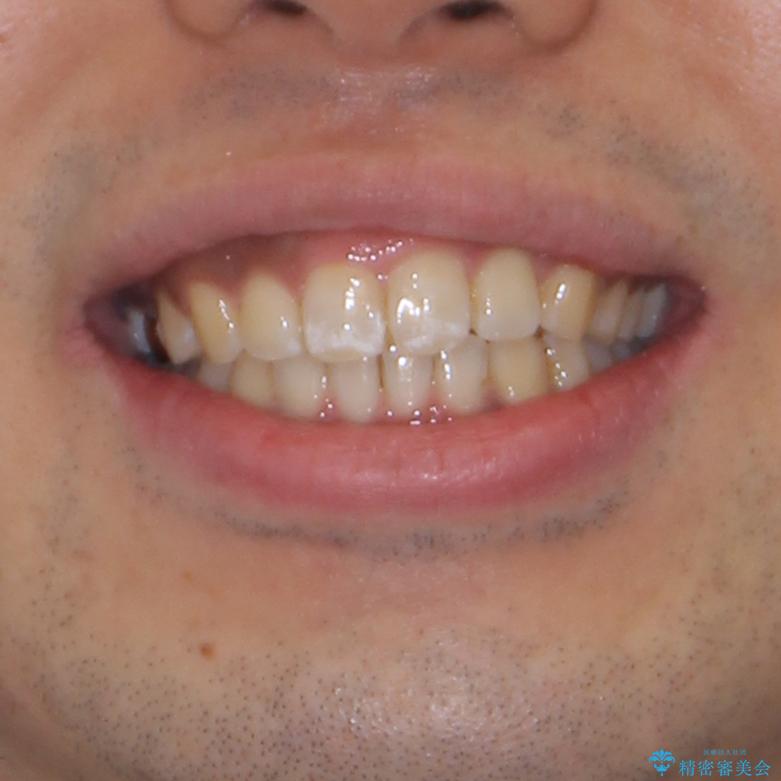

- 上下前歯部の叢生を気にして来院された患者様です。

レントゲン撮影により、右上奥歯が折れていることが分かりました。

患者様自身も何となく違和感を覚えていたとのことで、インプラント補綴治療を行うこととしました。

歯列不正は比較的軽微であったので、インビザラインによる矯正治療とし、矯正治療中にタイミングを見て抜歯とインプラント埋入を行う予定としました。